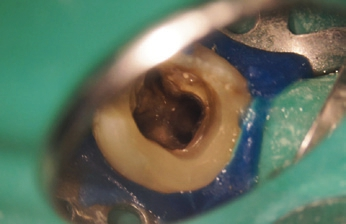

Im Anschluss an die Aufklärung über die Behandlungsoptionen wünschte die Patientin die endodontische Revisionsbehandlung. Nach intraligamentärer Anästhesie und Applikation von Kofferdam wurde unter dem OP-Mikroskop (OMS2350, Zumax Medical, Jiangsu/China) die Zugangskavität mit dem Diamantinstrument 15802* und anschließend dem EndoGuard (H269QGK*) angelegt. Die Darstellung des Pulpenkammerbodens und der Kanalorificien mit dem alten Obturationsmaterial erfolgte mit extralangen Rosenbohrern EndoTracer* (Abb. 2). Bei der intrakanalären Diagnostik konnte zudem in der distalen Wurzel ein zweites, bei der Primärbehandlung nicht aufbereitetes Kanalsystem dargestellt werden. Im koronalen Drittel wurde das alte Füllmaterial mit dem Endo ReStart-Opener (RE10L15*) entfernt, im mittleren und apikalen Drittel mit der Endo ReStart- Feile (RE05L21*), beides jeweils bei 300 Upm und einem Drehmoment von 1,8 Ncm ohne Einsatz eines Lösungsmittels. Die restliche Entfernung und das Sondieren der Kanalsysteme wurde mit Handfeilen bis zur ISO-Größe 012 (17525*) vorgenommen. Die Länge der Kanalsysteme wurde durch Handfeilen mit dem EndoPilot mobil endometrisch bestimmt (EP0013*). Es erfolgten die maschinelle Etablierung eines Gleitpfades mit dem PathGlider (PG03L25*) und die Aufbereitung der Kanalsysteme unter kontinuierlicher Spülung mit 6 % NaOCl (CanalPro NaOCl, Coltène/ Whaledent, Langenau). Die durch apikales Messen bestimmte Größe der Kanalsysteme ergab in den mesialen Kanalsystemen eine notwendige Aufbereitung bis zur ISO-Größe 035 und in den distalen Kanalsystemen bis zur ISO-Größe 045. Mechanisch aufbereitet wurde mit den F360-Feilen (F04L25*) im EndoPilot mobil bei 1,8 Ncm und 350 Upm (Abb. 3).